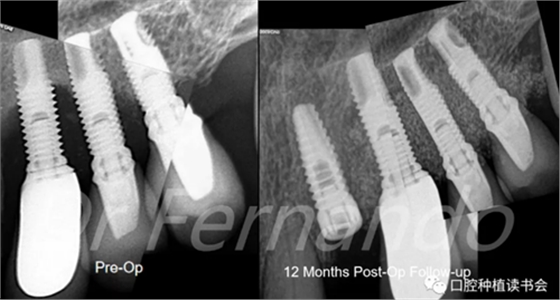

經(jīng)過12個月的隨訪,患者取得了良好的臨床效果,24位點種植體最終的曲面斷層片和根尖片,臨床顯示在種植體相應(yīng)部位的腭側(cè)病變?nèi)肯?,骨小梁恢?fù)良好。病人沒有任何不適癥狀(圖 24)。

圖24 術(shù)后12個月骨再生效果良好